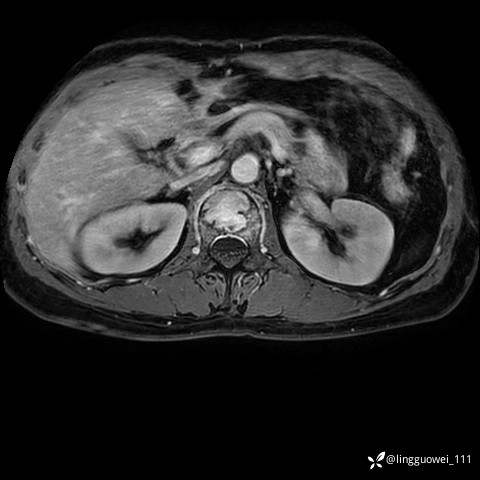

病例女,39岁,腰痛来诊,只有CT可能要鉴别诊断,而MR可以定性吗?

患者性别:女

患者年龄:39岁

主诉:腰痛

T2